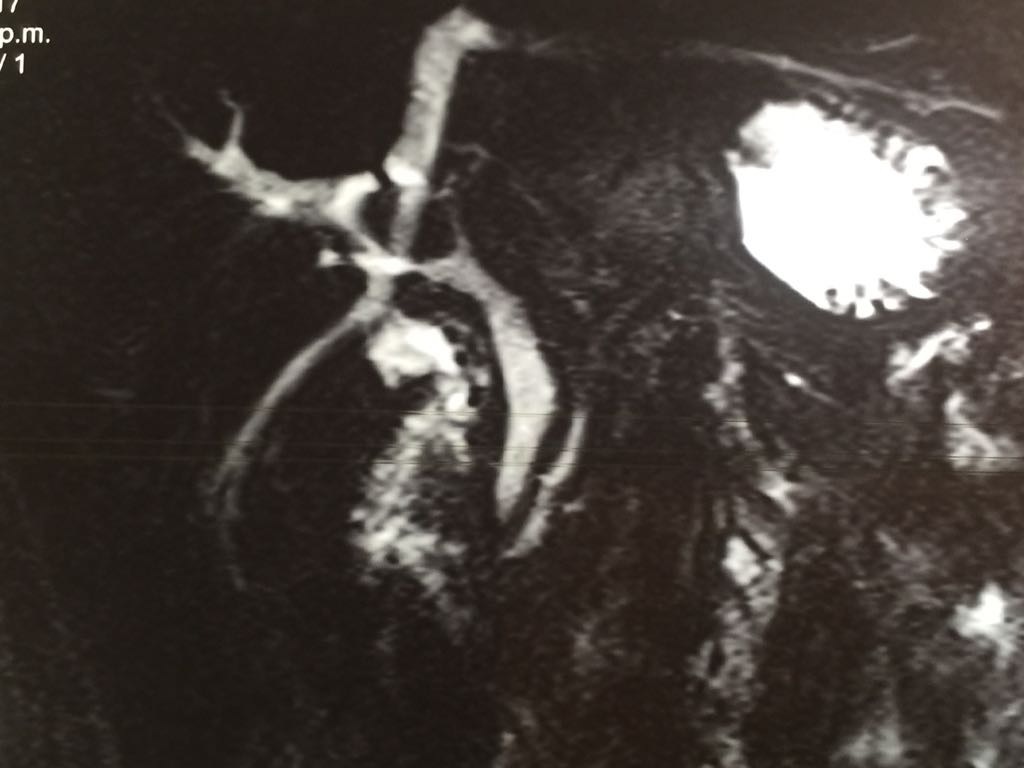

Image of the month